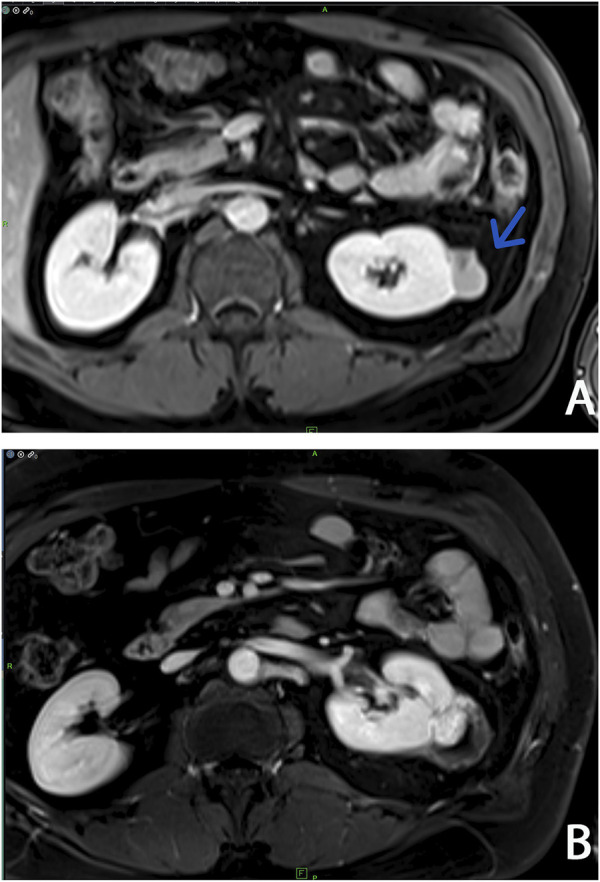

Case presentation: Years before the easy accessibility of the complete genetic workup in Hungary, a yearly abdominal MRI check-up was suggested preventively for a middle-aged man with multiplex cutaneous leiomyomata. During the follow-up period papillary type 2 renal cell carcinoma was diagnosed in the left kidney at an early stage, and a successful operation saved his life without the need for aggressive chemotherapy or immunotherapy. Immunohistochemistry of tumour tissue proved FH-deficient renal cell cancer. We discuss in short the current knowledge of pathophysiology and accessible therapies regarding this aggressive malignant tumour type in the kidney, which is usually detected in the advanced stage with early metastasis. We also highlight an early sign, i.e., solitary cystic alteration in the kidney, which can be preliminarily observed before malignant transformation, which was also described in mouse models. Sanger sequencing and Multiplex-Ligation-Dependent Probe Amplification (MLPA) analysis of the FH gene was completed in the affected son of the original proband, and Hereditary Leiomyomatosis and Renal Cell Cancer (HLRCC) was confirmed by demonstrating a large germline deletion in this family after years of observation.